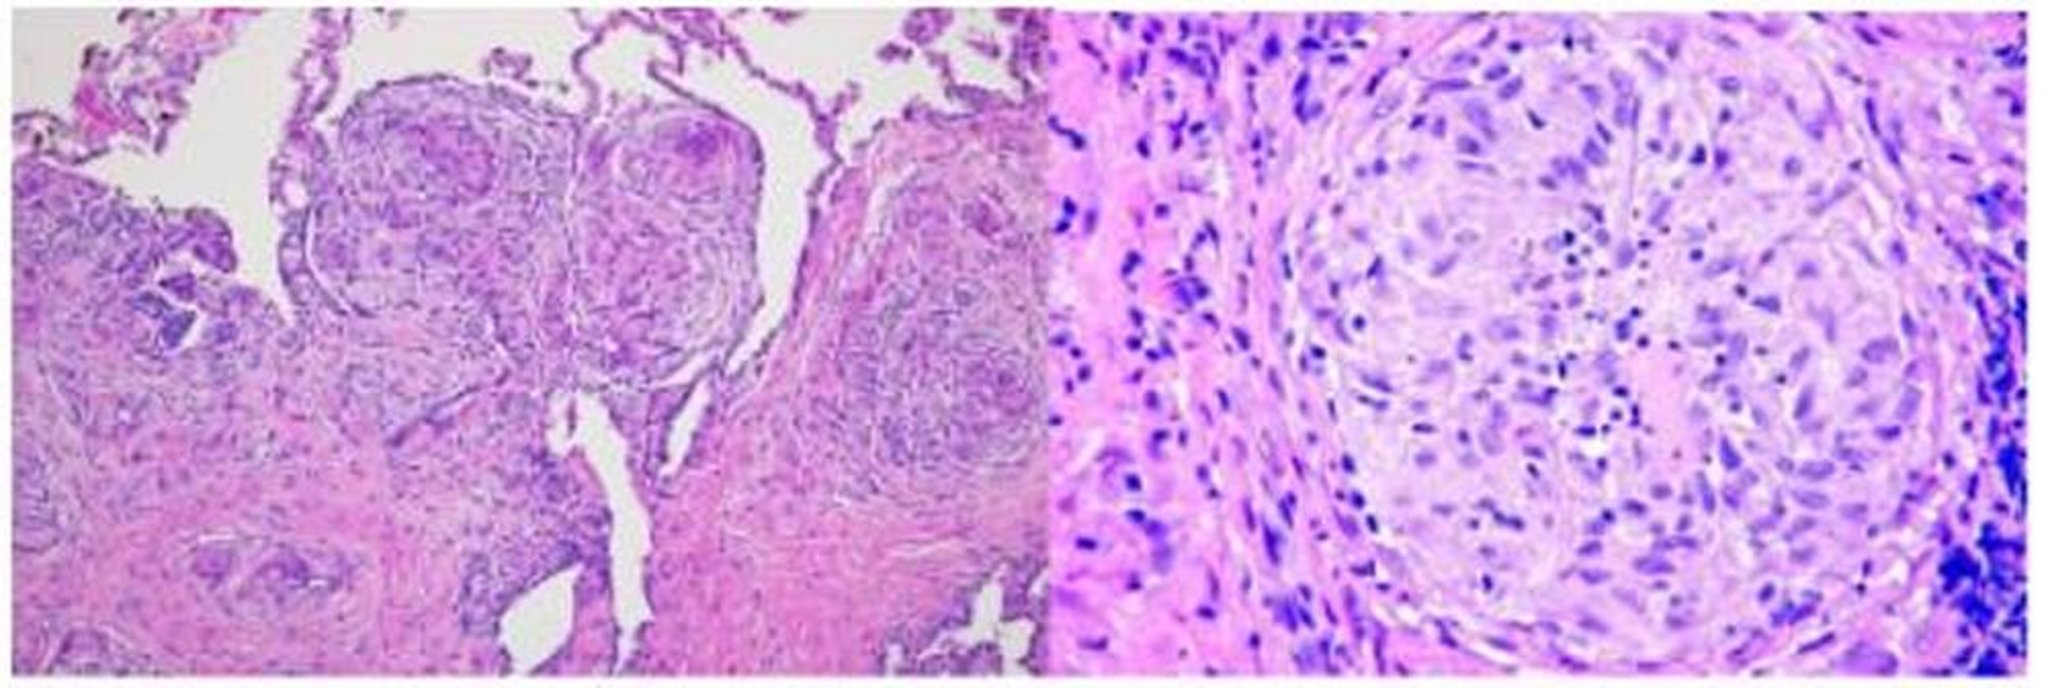

Саркоидоз (патологическая гистология)

На данном снимке в биоптате легкого пациента с саркоидозом видны гранулемы вдоль бронховаскулярного пучка (окраска гематоксилином и эозином, малое увеличение; слева) и саркоидная гранулема с многоядерными гигантскими клетками в центре гранулем (большое увеличение; справа).

Image courtesy of Birendra P. Sah, MD, FCCP.